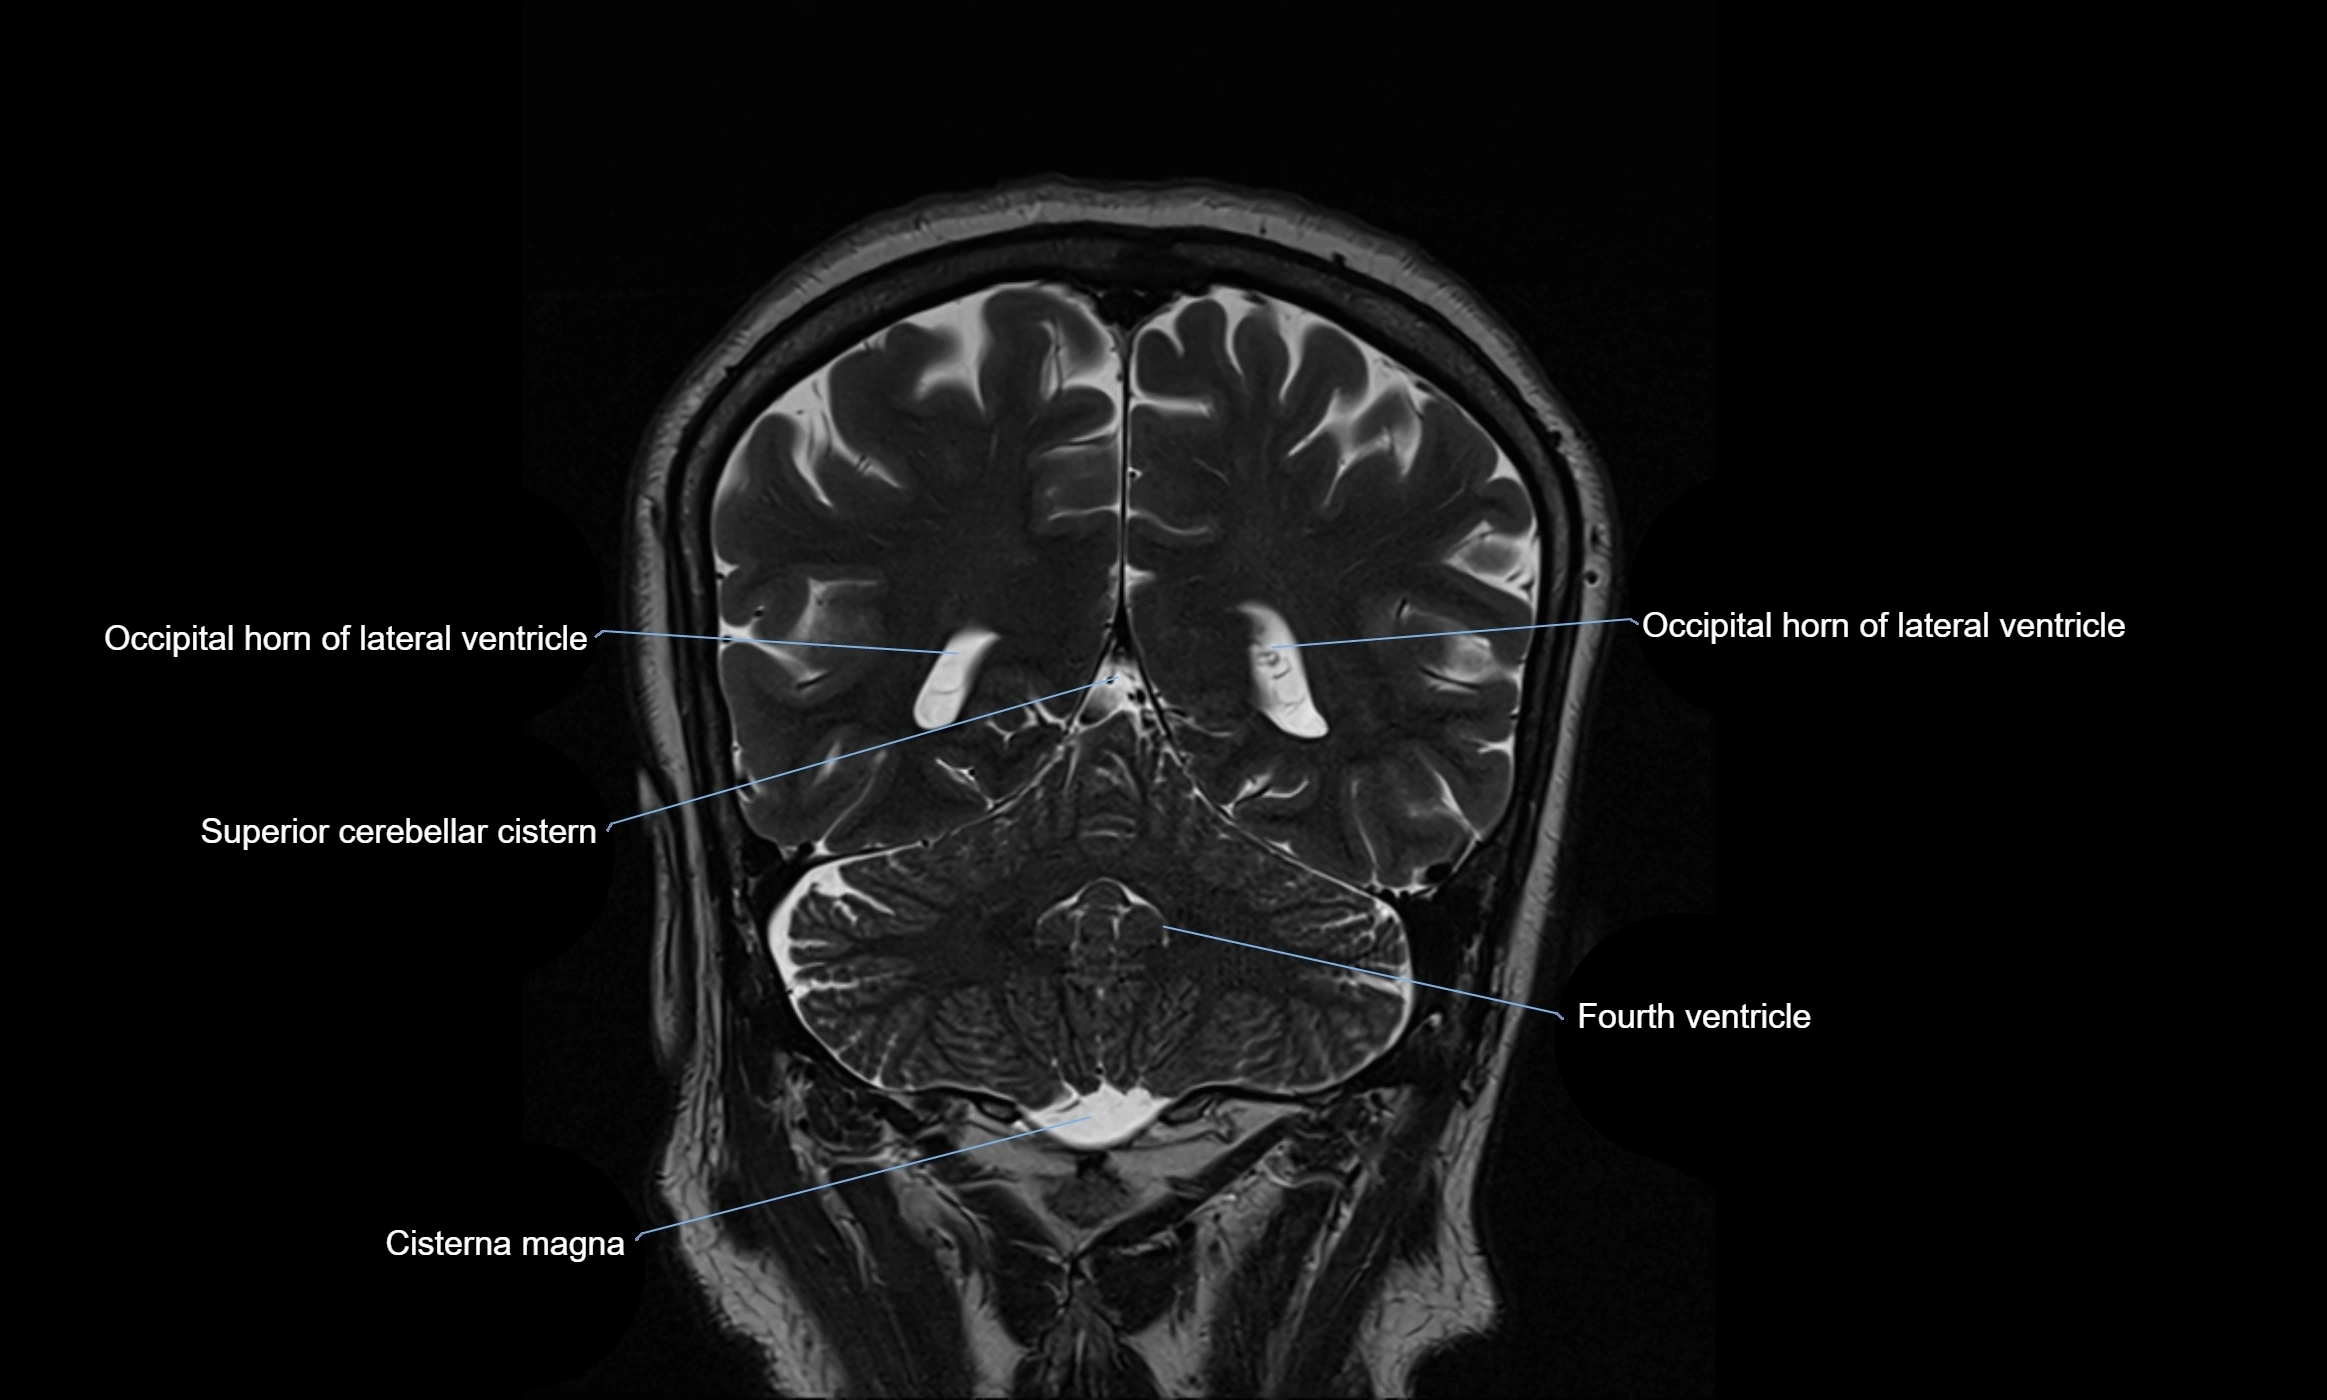

CT image

image